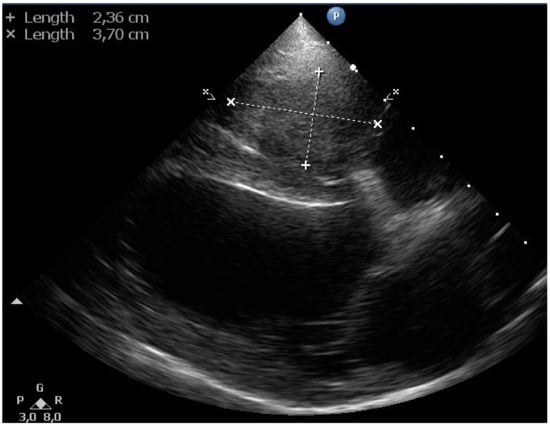

Echocardiography revealed a soft tissue mass (~2.5 × 3.7 cm) in the right ventricular lumen around the pacemaker electrode (Figure 5). No thrombus in the pulmonary trunk or the pulmonary artery branches was noticed.

Figure 5.

Two-dimensional gray-scale standard right parasternal 4-chamber long-axis echocardiographic image of a dog with a transvenous pacemaker lead shows a soft tissue mass of 2.36 × 3.70 cm (indicated by the calipers), which fills the right ventricular lumen completely.